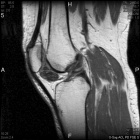

57 year old female presents with c/o L anterior knee pain x5 months. No hx of trauma.

Zoom image: Radiological image Radiological image.